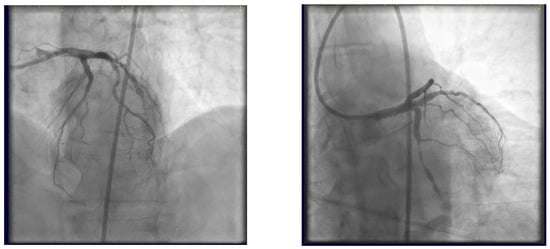

- Stenting the two most angled branches with stents (3.5/28 mm and 3.5/19 mm Sirolimus-eluting stents—Ultimaster, Terumo) sized to their distal diameter and slight protrusion in the main branch (Figure 16).